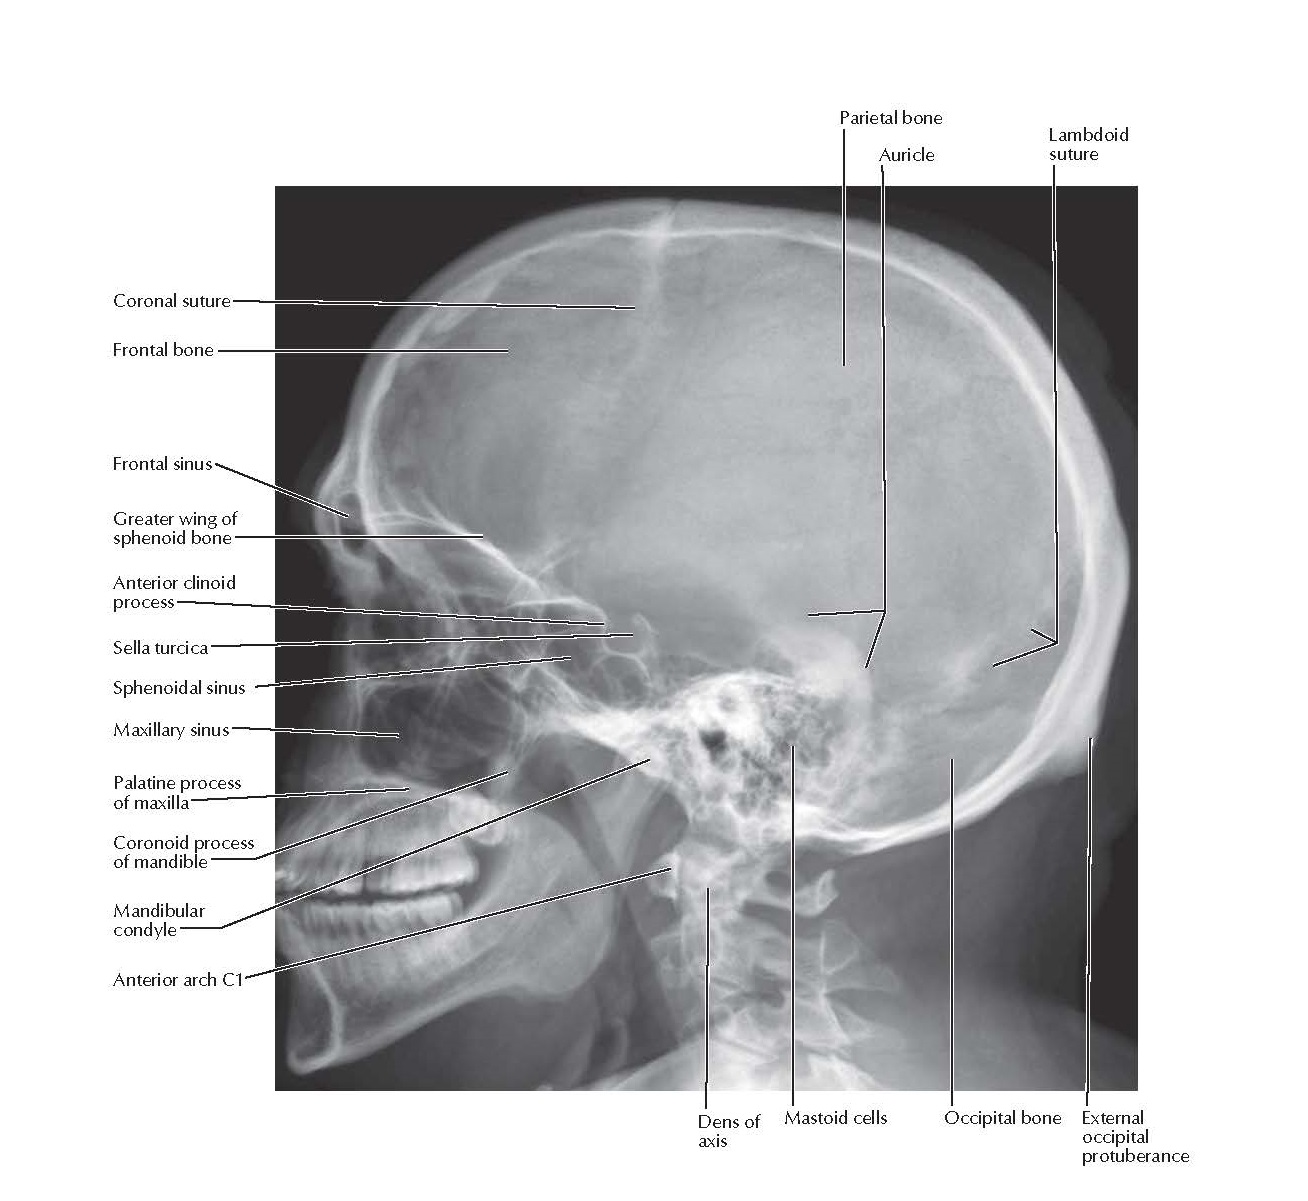

xray image of Human Skull lateral view for diagnosis skull fracture Skull X Rays Labeled  They are done to diagnose tumors, infections, foreign items, or bone injuries. The skull is the skeletal framework of the head of vertebrates formed by the cranium. The skull imaging study has a long list of indications that can practically be classified as trauma, benign or malignant focal skull lesions, and systemic pathologies affecting. This view provides an overview of. Skull X Rays Labeled.

Skull Lateral Radiograph Anatomy pediagenosis Skull X Rays Labeled  They are done to diagnose tumors, infections, foreign items, or bone injuries. The skull is the skeletal framework of the head of vertebrates formed by the cranium. The skull imaging study has a long list of indications that can practically be classified as trauma, benign or malignant focal skull lesions, and systemic pathologies affecting. This view provides an overview of. Skull X Rays Labeled.